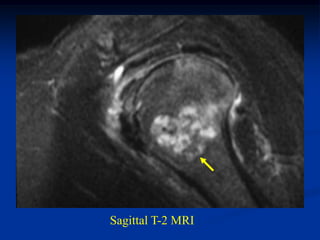

Case #554.1           Enchondroma and ganglion cyst

47 year male with shoulder pain for 6 months

ganglion

enchondroma                cyst

Coronal T-2 MRI

Sagittal T-2 enchondroma   Sagittal T-2 ganglion

Two different T-2 axial cuts showing the enchondroma

and the right cut shows the ganglion